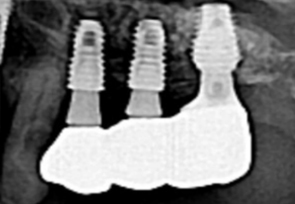

미국치과 임플란트 학회(AAID)의 인정의(AF. Associate.Fellow)인 일등플란트치과의 한순일 대표원장이 다 년간의 많은 임상경험 노하우를 바탕으로 구강 상태에 따른 적합한 뼈이식을 통해 임플란트에 적합한 뼈의 두께를 확보한 후 식립을 합니다.

잇몸뼈에 심은 임플란트가 잇몸뼈에서 단단히 고정되면 인공치아 보철물을 올려 치아부분을 완성합니다. 일등플란트 치과는 병원 내에 별도의 기공소가 있어 나의 자연 치아와 가까운 자연스러운 보철물을 빠르고 꼼꼼하게 제작합니다.